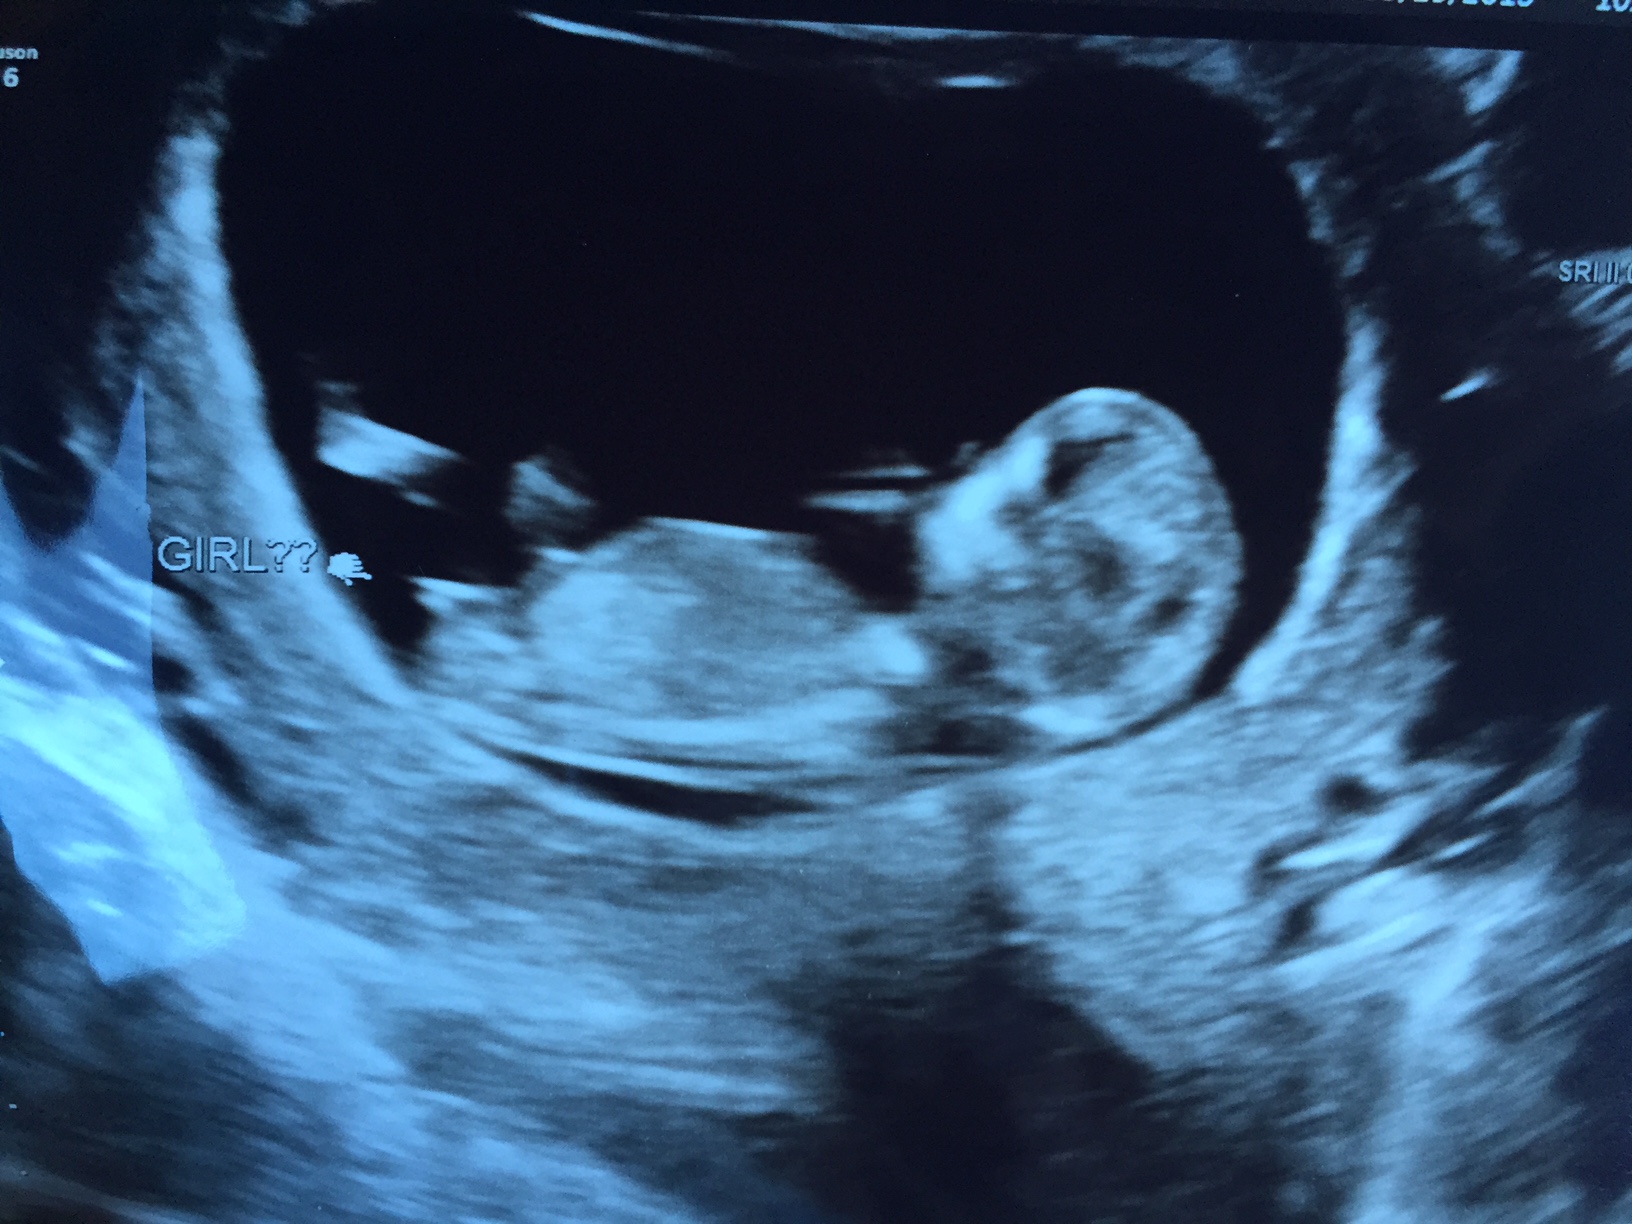

Hello! Great nub shot ... guesses please!!!!

Hi! I've been waiting for this ultrasound for forever it seems like. This was at 11w1d. The ultrasound tech was happy to give me a nub shot and her own guess, too. I also included a skull pic for skull theory. Let me know what you think! I swayed girl, and have two beautiful boys I adore. We are happy with whoever this LO is!!